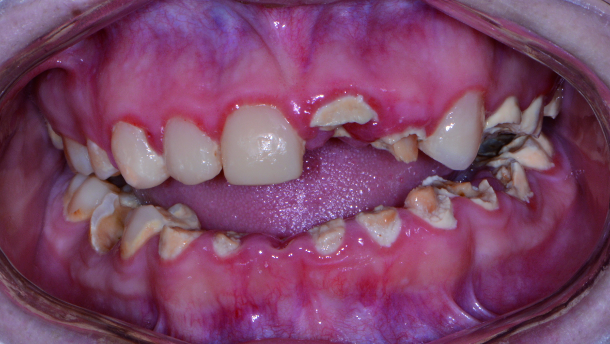

A patient presented to my practice for a consultation wanting to restore her smile (Fig. 1). She complained of generalised discomfort in her entire dentition; probably due to the rampant caries and infection that was already present (Figs. 2–5). Having already visited multiple providers for an evaluation, she was very frustrated with conflicting treatment options offered. Either the suggested treatment would require multiple surgical and restorative visits that would extend for a very long time or dental treatment would require a team approach where little coordination by dentist and specialist was communicated to the patient. Since many of these options did not appeal to her, the patient decided to have me provide comprehensive treatment that would include extractions, bone leveling, grafting, dental implant placement, immediate provisionalisation and prosthetic rehabilitation within my own practice.

A CBCT scan was taken to accurately treatment plan this case to make certain that no complications would arise from doing all the procedures (extract, graft and implant placement) within one visit. Since her entire dentition had rampant caries present, her treatment would require extracting teeth #2–15 and #18–31, as well as the impacted third molars (teeth #1, 16, 17, 32) to avoid any further complications in the future.